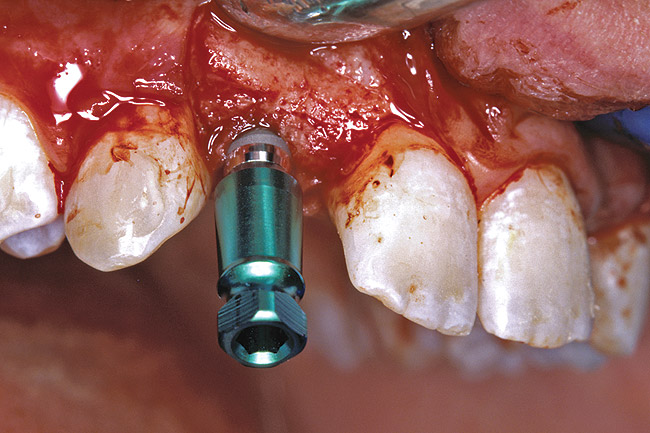

Before the day of surgery, the patient was seen by the orthodontist for the removal of the orthodontic brackets. The patient still was not pleased with the position of the two centrals, and it was determined that this would be addressed after implant placement (Figure 26). The anatomical variations of the crestal tissue and lack of interdental papilla can be appreciated in the close-up views of the right and left sites (Figure 27 and Figure 28). There were no surprises on the day of surgery as all of the decisions were made during the planning phase, before the scalpel ever touched the patient. The occlusal view of the CT 3D model revealed the wider alveolar ridge on the right side and thinner crest on the left side (Figure 29). This was confirmed when the full-thickness mucoperiosteal flaps were elevated, and the underlying bone revealed (Figure 30). The tooth-borne templates were designed to facilitate the drills and drilling sequence specific to the diameters of the predetermined implants (Figure 31). Each template contained an embedded 5-mm long stainless steel tube, which was approximately 0.2-mm wider than each drill (just wide enough to allow for the drills to rotate freely). Once positioned over the natural teeth, the template was secure and offered precision accuracy in transferring the implant locations from the original software-designed plan, allowing the potential for internal and external irrigation (Figure 32).

The 3.7-mm diameter Tapered Screw-Vent implant drilling sequence requires three drills: pilot, intermediate, and final sizing. Thus, three separate templates were fabricated to accommodate these sizes. The templates were removed easily and replaced with the next sequential size in less time than it takes to change the drill on the surgical handpiece. After the osteotomies had been completed, the implants were delivered to the site (Figure 33 and Figure 34). For this internal hex connection implant, the author recommends that the flat of the anti-rotational hex be positioned to the facial for proper orientation of the restorative components (Figure 35). Pre-prepared margins were created from a milled titanium fixture mount transfer post, which was delivered to the implant as support for an immediate transitional restoration. The facial “dot” helped to confirm the orientation of the abutment to the facially positioned flat side of the internal hex connection (Figure 36). Before cementation of the transitional acrylic restorations, a closed-tray, fixture-level impression was made, and a soft-tissue model was fabricated.

Figure 33  VIRTUAL PLANNING AND SURGERY After the osteotomies were completed, the implants were placed.

Figure 33

Figure 34  VIRTUAL PLANNING AND SURGERY After the osteotomies were completed, the implants were placed.

Figure 34